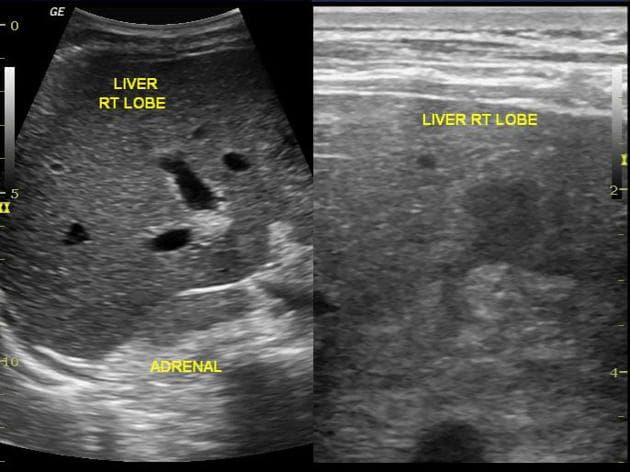

Có 2 tổn thương gan giảm tỷ trọng (hypodense), kích thước nhỏ, chưa xác định được bản chất tại phân đoạn 6 dưới màng gan.

Các tổn thương giảm tỷ trọng chưa xác định tại phân đoạn VI gan (indeterminate hypodense lesions segment VI of the liver) cũng có thể được đánh giá thêm trong lúc chụp CT gan nhiều thì.

Chronic Subcapsular Hepatic Hematoma (Khối máu tụ dưới vỏ gan mạn tính)

Hepatic Hematoma in HELLP Syndrome (Khối máu tụ gan trong hội chứng HELLP)